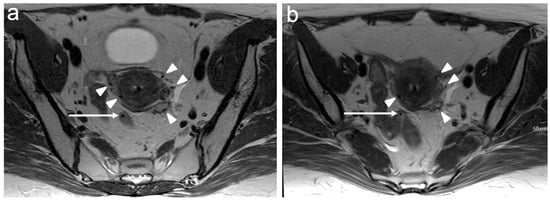

6. FIGO Stage III

7. FIGO Stage IV